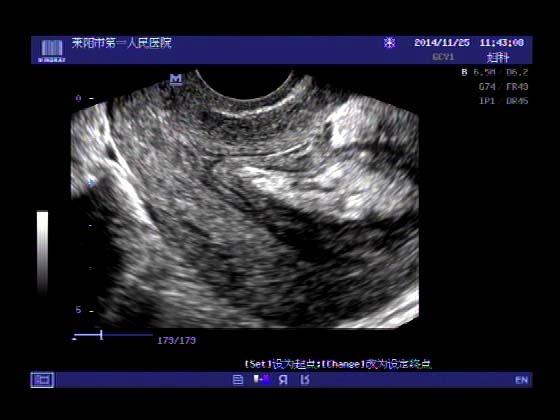

超声入门贴379---------粘膜下肌瘤(阴超的魅力)

女,43岁,月经量多3个多月,加重一个月

外院彩超检查提示:子宫后肌壁略高回声团------肌瘤?息肉?,盆腔少量积液

今天来我院检查:

巧妇难为无米之炊,经腹部超声确实很难定,阴超一目了然,乡镇医院诊断水平的提高更迫切的需要高档仪器的引进!